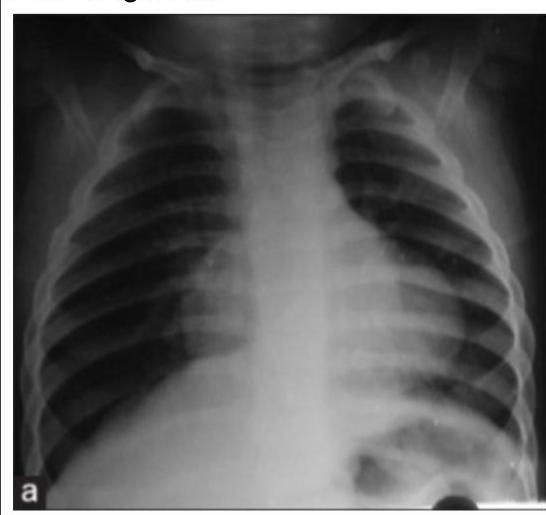

A young child presented with mild intermittent upper abdominal pain. X-ray is given below. What is the diagnosis?

Explanation: ***Morgagni hernia*** - The X-ray shows a **gas-filled lesion** in the **right cardiophrenic angle**, which is characteristic of a Morgagni hernia, where abdominal contents (often colon or omentum) herniate through the foramen of Morgagni. - The mild intermittent **upper abdominal pain** in a child is consistent with the infrequent or non-specific symptoms these hernias can present, as they are often discovered incidentally. *Bochdalek hernia* - **Bochdalek hernias** typically occur posteriorly and laterally, predominately on the **left side**, and are usually identified in the **neonatal period** with severe respiratory distress. - The radiographic appearance would be of abdominal contents (bowel loops, liver, spleen) largely filling the ipsilateral hemithorax, causing significant mediastinal shift, which is not seen here. *Gastric volvulus* - **Gastric volvulus** involves abnormal rotation of the stomach, often presenting with acute symptoms like **epigastric pain, vomiting, and inability to pass a nasogastric tube (Borchardt's triad)**. - Radiographically, it would show a **distended stomach** with an abnormal position, often high in the chest, but without the distinct localized air-filled mass in the cardiophrenic angle. *Eventration of diaphragm* - **Diaphragmatic eventration** is an abnormal elevation of part or all of an intact hemidiaphragm, usually due to muscular hypoplasia. - The X-ray would show a **uniformly elevated hemidiaphragm** with normal continuity, and there would be no discrete air-filled structures above the diaphragm to suggest herniated bowel.